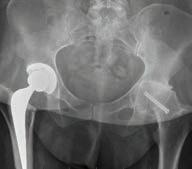

Calls for breast density reporting

All

women having routine mammography should be told if they have dense breasts and are of greater risk of breast cancer, the peak body for radiologists says.

In a position statement published last December, the Royal Australian and New Zealand College of Radiologists joined calls for widespread breast density reporting to inform patients of their particular risk.

Breast density — the ratio of fibro-glandular tissue to fatty tissue — can be an independent risk factor for breast cancer and can also affect the accuracy of mammogram reporting, because dense tissue and tumours both appear white in mammograms.

About 40-50% of women have dense breasts, but currently there is no national policy on optimal management of notifying women of breast density, with only Western Australia and South Australia requiring patients to be assessed and notified.

Last year, the US Food and Drug Administration introduced a requirement that breast density be reported on all mammogram results nationwide, and for that report to go to both clinicians and patients. Previously this was the rule in some states, but not in others.

There are now calls to have a consistent national policy on breast density notification across Australia.

“While a future risk-based model for breast cancer screening is being developed, RANZCR recommends mandating the reporting of breast density in both screening and diagnostic settings,” the college statement said.

Higher risk

One in 10 Australian women are estimated to have Breast Imaging-Reporting and Data System (BI-RADS) category D density, or extremely dense breasts.

“Studies have demonstrated that extreme (mammographic breast density) is associated with a 2.1fold increased risk of breast cancer compared with the average risk scattered category of BI-RADS category B,” the RANZCR said.

Meanwhile a new Australian trial is looking at the potential harms and benefits of notifying women of the risks associated with breast density during routine breast screening.

A randomised control trial undertaken in Queensland aims to examine the longer-term effects of notifying women about breast density in relation to breast cancer risk factors.

The trial, which started last September in BreastScreen Queensland clinics, has been outlined in a study protocol published in the Medical Journal of Australia

The researchers said there had been continued international debate surrounding the pros and cons of widespread breast density notification. They hope the evidence from the study would guide best practice and policy for breast screening in Australia and abroad.

The trial is a world-first in assessing the impact of notification (versus not) using a randomised design, and to also test different ways of telling women that they have dense breasts on mammograms.

It will look at the benefits and harms of notification, including the effect over time – two years or more.

The study will look at psychological outcomes of notifying patients – whether they feel anxious, confused or informed – and also whether it influences them to have follow-up GP consultations and supplemental breast screening.

Researchers hope the findings will help BreastScreen Australia to develop best practice policies for notifying women of breast density and to find the most effective way.

ED: Congratulations to BreastScreen WA, which turns 35 this year after starting as a pilot program in 1989. It targets women aged 50-74 years, offering free screening every two years, but women can access it from the age of 40. Go to www.breastscreen.health.wa.gov.au